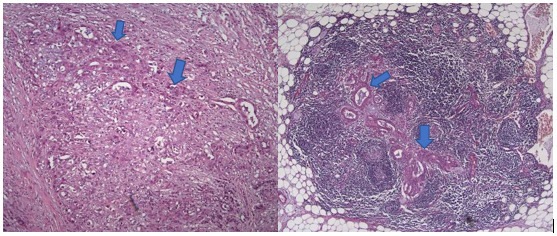

In November 2018, a pancreaticoduodenectomy (Whipple procedure) was performed. Complications after surgery were a hemoperitoneum, which was managed surgically, and peripancreatic fluid collection, which was treated with antibiotics. The postoperative histological examination of the tumor sample confirmed a moderately differentiated (G2) acinar adenocarcinoma of the pancreatic head, diameter 2.3 cm (pT2), with metastases in 1 out of 12 peripancreatic lymph nodes (N1) and the presence of perineural invasion (Pn1), without angioinvasion (V0), and negative resection margins (R0) (Figure 2).